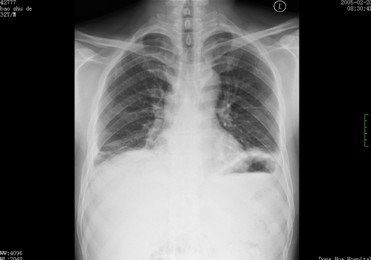

2. 脓胸:胸水WBC>10,000/mm3(图)

http://webres.medlive.cn/upload/000/062/246